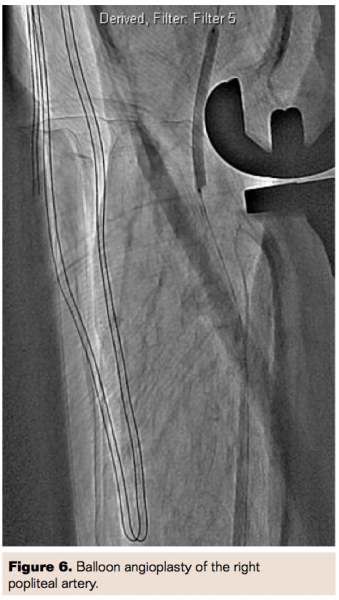

The patient was taken to the cardiac catheterization lab and initial diagnostic angiogram through the right radial approach showed right popliteal artery and right anterior tibial occlusion (Figure 5). The patient was scheduled the next day for endovascular intervention of the right popliteal artery.

Balloon angioplasty of the right popliteal artery was performed from the groin access using a Charger 5.0 mm x 60 mm balloon followed by a Charger 6.0 mm x 60 mm balloon (Boston Scientific) with excellent results. However in the right lateral view while balloon was inflated, there was a hint of suspicion that the implant might be pushing on the popliteal artery (Figure 6). It was decided at that time not to deploy a Supera stent (Abbott Vascular), which is FDA approved for this location.